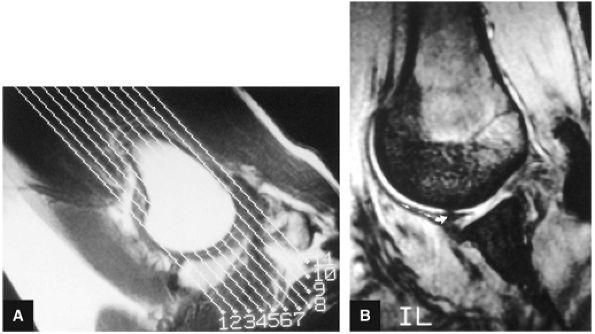

FIGURE 8.7 ● (A) Normal central point (red cross) of glenohumeral rotation with arm positioned in abduction and external rotation. This position of function is achieved by placing the hand behind the head with the patient in the supine position. (B) Axial oblique ABER (abduction and external rotation) anatomy illustrated at the level of the IGHL labral complex posterior to the ABER section through the supraspinatus tendon. The MGHL and conjoined rotator cuff tendon are visualized superior to this section, whereas the inferior labrum and teres minor tendon are demonstrated inferior to this section in the ABER sequence.

FIGURE 8.8 ● Functional anatomy of the inferior glenohumeral ligament (IGL). (A) A coronal localizer obtained with the arm placed in 90° of abduction (i.e., the position of function of the IGL) and external rotation. (B) The corresponding axial image through the glenohumeral joint shows a taut IGL (small straight arrows) and intact anterior labrum (curved arrow).